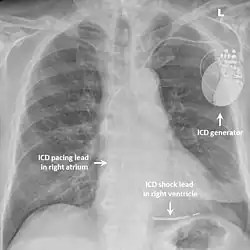

Desfibrilador automático implantable

En aquellos con síndrome de QT corto que ya han experimentado un ritmo cardíaco anormal potencialmente mortal, como la fibrilación ventricular, se puede recomendar un desfibrilador cardioversor implantable (DCI) para reducir la posibilidad de muerte súbita[3] Este dispositivo se implanta debajo de la piel y puede monitorear continuamente el ritmo cardíaco. Si el dispositivo detecta una alteración peligrosa del ritmo cardíaco, puede administrar una pequeña descarga eléctrica con el objetivo de restablecer el ritmo. Implantar un DCI en alguien con síndrome de QT corto que aún no ha experimentado una arritmia potencialmente mortal es más controversial, pero se puede considerar.[6][1]